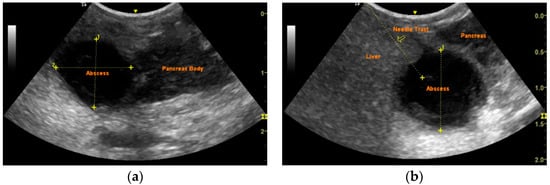

Successful Management of a Pancreatic Abscess in a Dog with Juvenile Diabetes Mellitus Through Ultrasound-Guided Drainage and Medical Therapy

2. Case Description